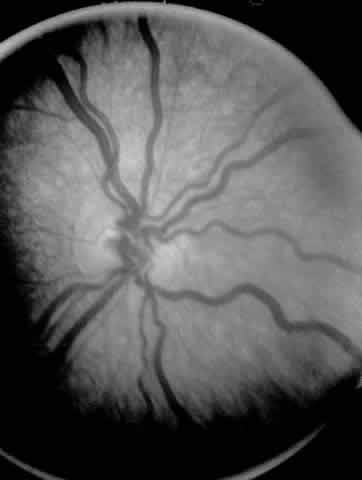

When first assessing a child's retinal detachment, one must judge the amount of effusive versus tractional detachment (Figs. 4 and 5). Scleral buckling would be considered for the child who shows a predominately effusive stage 4B detachment as opposed to a stage 4 predominately tractional detachment, for which lens-sparing vitrectomy may be recommended.24 For a child who has a great deal of retrolenticular touch, lensectomy/ vitrectomy and membrane peeling would be recommended. It appears that the “window” for lens-sparing vitrectomy may be rather brief. In one series, the postconceptual age of the lens-sparing vitrectomized eyes was 42.6 weeks, as opposed to 46.9 weeks for eyes that needed lensectomy/vitrectomy and membrane peeling. This small time difference in the postconceptual age shows the often rapid evolution of this detachment from one in which the lens is salvageable to one in which the lens is unsalvageable. This highlights the need for timely screening of eyes, identification of eyes with progressive disease, and rapid intervention.25

Fig. 4. A predominantly effusive stage 4B retinal detachment.

Fig. 5. A predominantly tractional stage 4B retinal detachment.